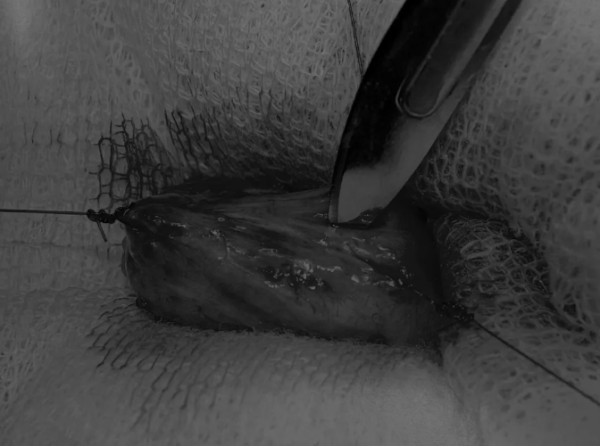

手术方法 在中线开腹手术后,确定膀胱,将其取出并隔离(图1)。为了使膀胱持续暴露,可在膀胱中线两侧各放置一根固定缝线(图2)。 在切开膀胱前,应用膀胱穿刺的方法获取尿液样本进行微生物培养。 图2 在手术过程中,还需要另外两根固定缝线来保持膀胱切开术的膀胱边缘处于暴露状态 在牵引缝线之间选择血管扩张较差的区域用手术刀切开膀胱壁(图3)。在牵引缝合线之间用手术刀在血管不良的区域做切口。切开膀胱壁后,膀胱内的手术可按手术方案实施,例如取出结石(图4)。 图3 避开主要的膀胱血管,做一个尽可能小的切口 切口可以在膀胱背侧或腹侧进行,避免对大血管的损伤。 图4 这张图显示了从膀胱中取出的大量结石 完成膀胱内冲洗后,应通过导尿管反向冲洗膀胱;砂样结石和血块会被冲到切口表面(图5) 图5 通过导尿管注入无菌生理盐水反向冲洗,可以去除微小的结石(箭头)和夹杂在膀胱黏膜皱褶中的砂样结石,以及可能在手术中形成的血块 膀胱创面采用单丝合成可吸收缝线缝合,采用外科医生习惯的缝合方式,但注意不要刺穿黏膜层(图6、图7)。 图6 使用简单的连续缝合。尽量不要用针刺穿黏膜层(箭头),以免缝线与尿液接触 图7 缝线应带入足够的切口两侧的膀胱组织,以确保在膀胱充盈时,没有伤口裂开 图8 这张图显示了通过导尿管注射的盐水,在缝合的切口处没有液体渗漏 关膀胱后,将无菌盐水注入膀胱腔内,检查是否有渗漏(图8)。 膀胱切开术闭合创口后,冲洗腹腔,以清除可能进入腹腔中的任何尿液、沙样结石或血凝块。 然后膀胱上覆盖小片的网膜,开腹手术伤口以通常的方式闭合。 手术视频 长按识别二维码观看视频